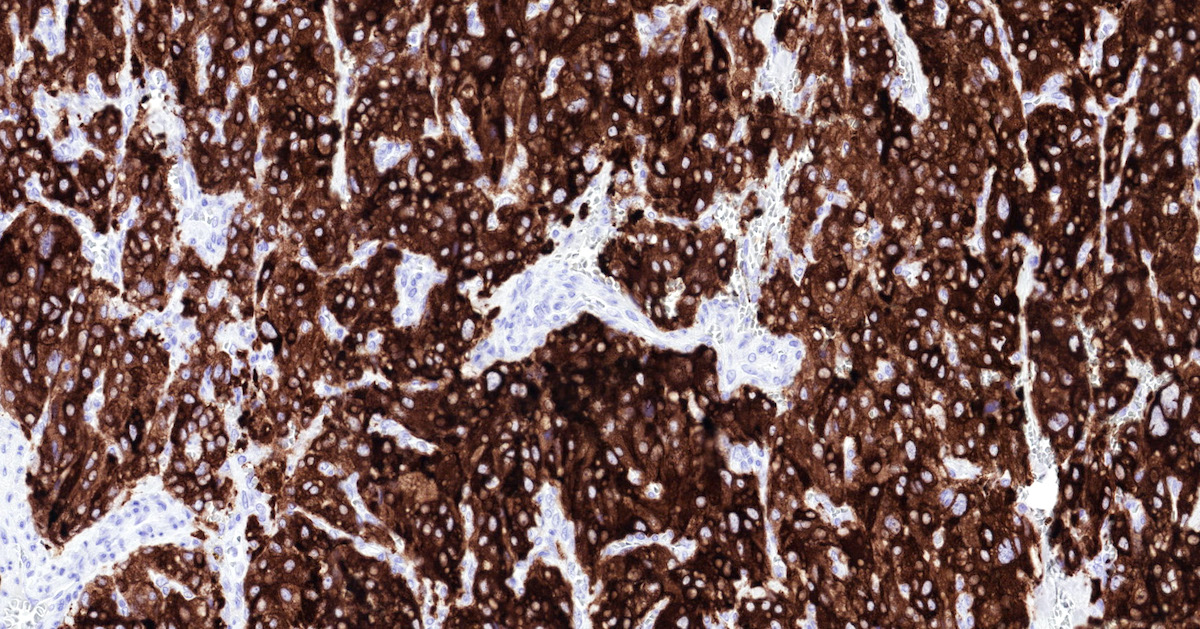

Microscopic (histologic) images

Contributed by Luvy Delfin, M.D. and Sylvia L. Asa, M.D., Ph.D.

Positive stains

- INSM1 (diffuse nuclear) (Am J Surg Pathol 2018;42:665)

- Chromogranin A (can be only focal or perinuclear dot-like golgi pattern)

- Synaptophysin (Histol Histopathol 1993;8:429)

- CD56 (Endocr Pathol 2002;13:149)

- S100 may be diffusely positive (J BUON 2018;23:1540)

- GATA3 (diffuse nuclear) (Hum Pathol 2020;103:72, Am J Surg Pathol 2014;38:13, J Clin Med 2018;7:280)

- Tyrosine hydroxylase (critical enzyme required for catecholamine synthesis; usually diffuse and strong in sympathetic paragangliomas, may be weak or focal in parasympathetic tumors) (Hum Pathol 2020;103:72)

- Dopamine beta hydroxylase and phenylethanolamine N methyltransferase (PNMT) (epinephrine producing tumors) (see Diagram below) (Neuroendocrinology 2015;101:289, J Clin Med 2018;7:280)

- Sustentacular cells: S100, GFAP and SOX10 (Hum Pathol 2020;103:72)

- Ectopic immunoexpression of hormones: serotonin, ACTH, CRH, VIP, leu enkephalin substance P, gastrin, somatostatin, vasopressin, MSH and calcitonin (Arch Endocrinol Metab 2017;61:291, J Clin Endocrinol Metab 2021;106:598, Endocr Pract 2014;20:e145, Ann Intern Med 1979;91:208)

- IHC surrogate markers for germline mutations:

- SDHB or SDHA expression loss: germline SDHx mutations (Lancet Oncol 2009;10:764)

- FH expression loss: germline FH mutation (HLRCC) (Hum Pathol 2018;71:47)

- Carbonic anhydrase IX (CAIX) expression: 80% of VHL mutation (Mod Pathol 2020;33:57)

- Inhibin alpha: any hypoxic pathway disease (SDHx, VHL, etc.) (Am J Surg Pathol 2021;45:1264)

- Reticulin highlights the nesting pattern (Int J Gynecol Pathol 1991;10:203, Exp Toxicol Pathol 2013;65:631)

Contributed by Luvy Delfin, M.D. and Sylvia L. Asa, M.D., Ph.D.